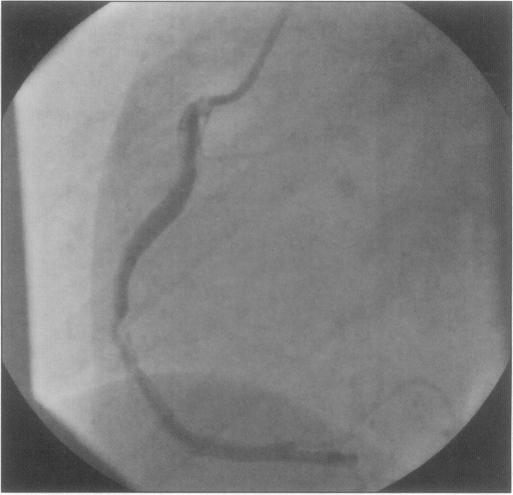

Coronary artery dissection following blunt chest trauma is rare. We report the case of a 43-year-old woman who was admitted with a subacute inferior myocardial infarction due to dissection of the right coronary artery. Ten days earlier, she had sustained a minimal chest trauma. The literature is reviewed and management is discussed.

钝性胸部创伤后冠状动脉夹层很少见。我们报告一例43岁女性患者,因右冠状动脉夹层导致亚急性下壁心肌梗死入院。10天前,她遭受了轻微的胸部创伤。本文回顾了相关文献并讨论了治疗方法。